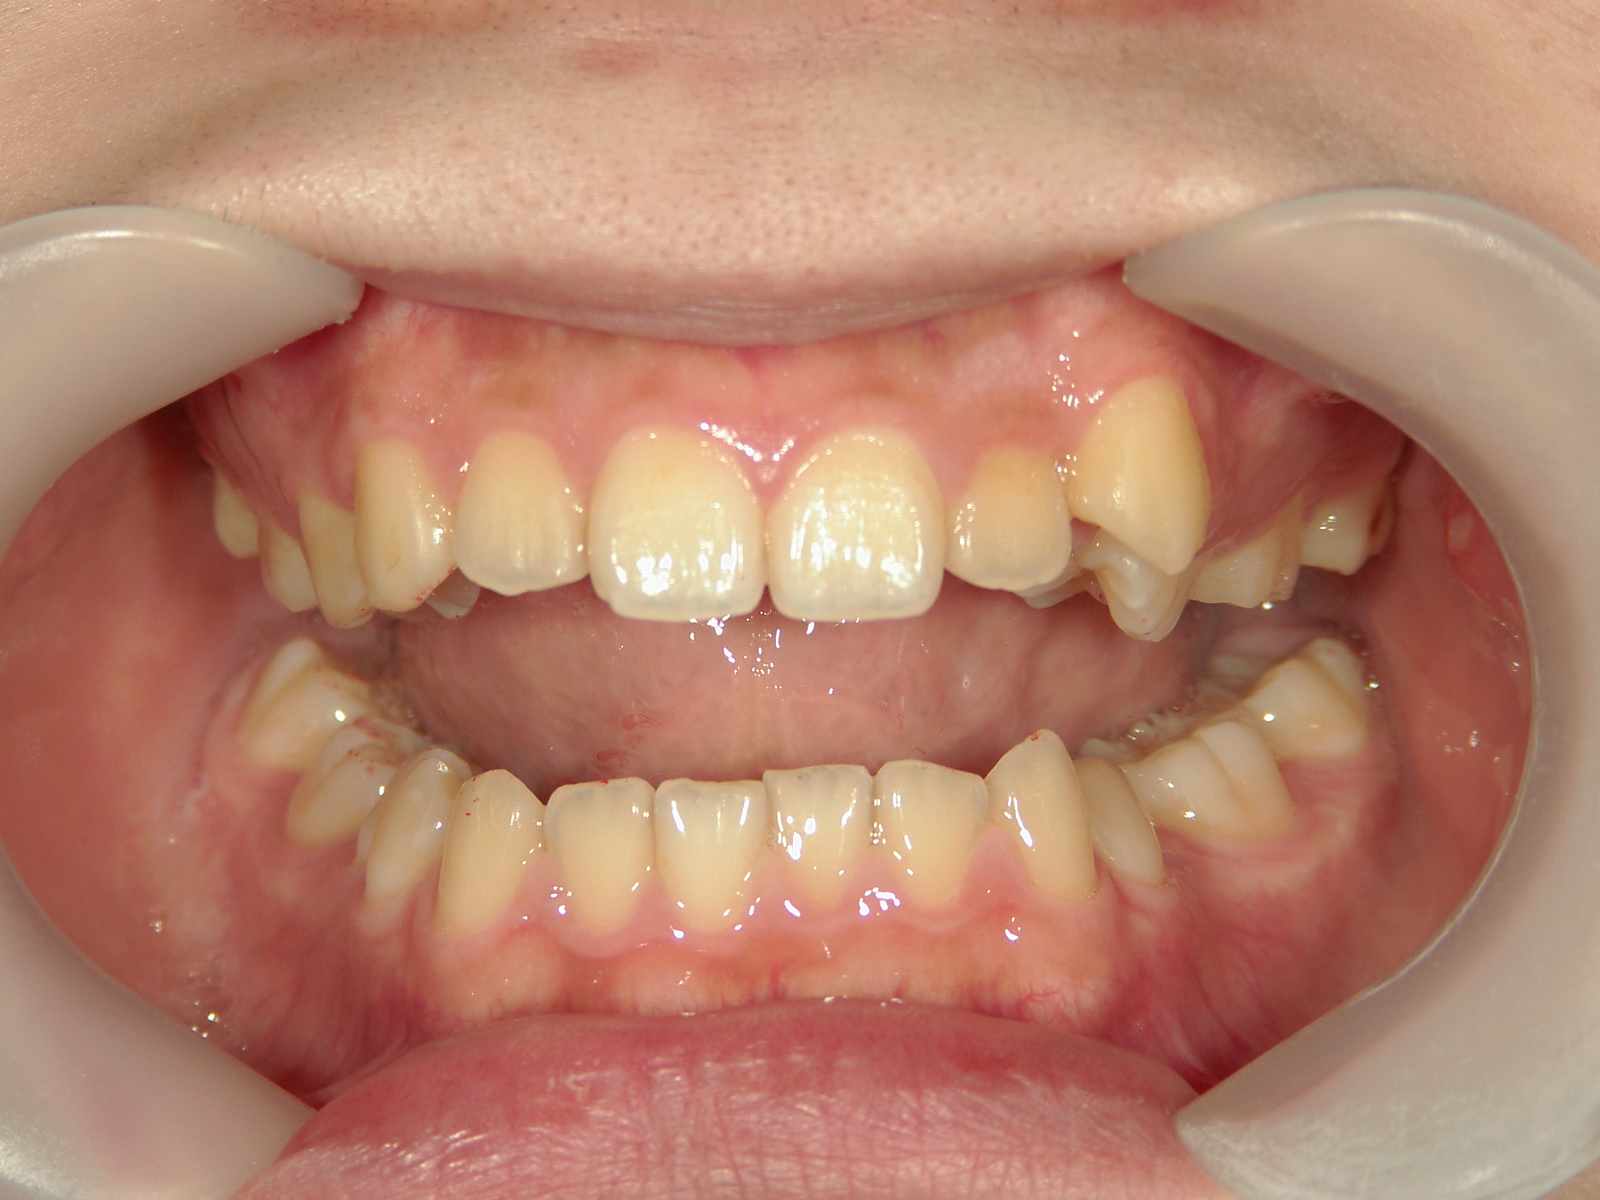

インビザライン矯正 症例(19)

主訴: 左上犬歯が出ているのが気になる